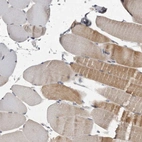

Immunohistochemistry analysis in human parathyroid gland and skeletal muscle tissues using Anti-MAN2A1 antibody. Corresponding MAN2A1 RNA-seq data are presented for the same tissues.